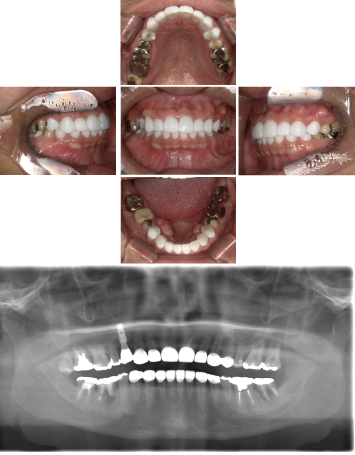

50代 インプラント治療(右上3左上3のみGBR)

| 年代・性別 | 50代・男性 |

|---|---|

| 主訴 | 入れ歯が合わず毎日ヨーグルトしか食べることができないので、しっかり咬めるインプラントにしたい。 |

| 部位 | 右下⑦⑥5④ 上顎③2①①2③ 左下67 |

| 治療期間 | 約9ヶ月 |

| 費用 | ¥4,273,500(税込) |

| 副作用・リスク |

|